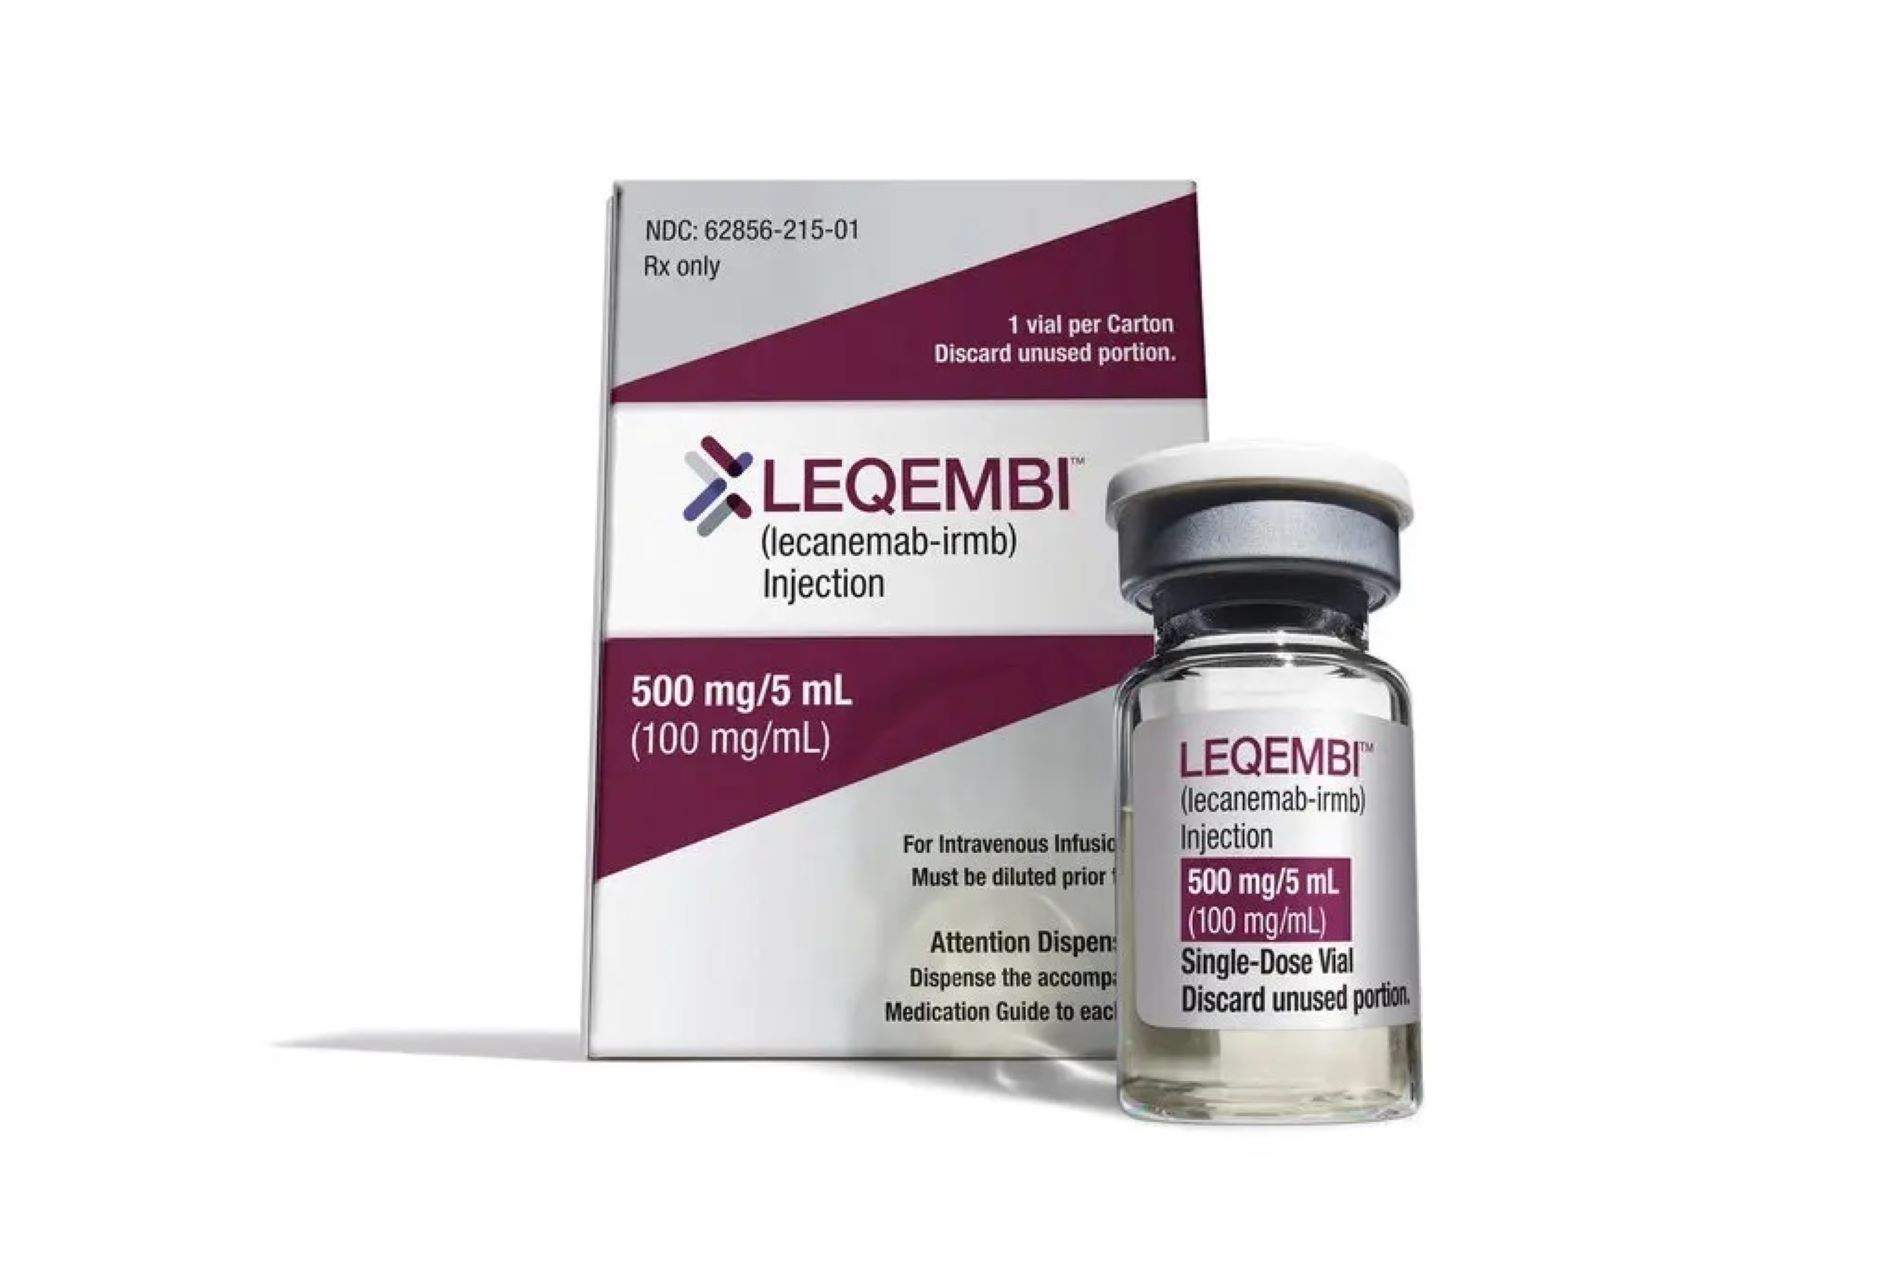

La Comisión Europea autoriza el uso del fármaco lecanemab para las primeras fases de la enfermedad de Alzheimer

Miércoles, 16 de abril de 2025 - 18:12

La EMA rechaza la licencia para Kisunla, una inyección pensada para tratar al Alzhéimer en etapas tempranas

Viernes, 28 de marzo de 2025 - 18:42